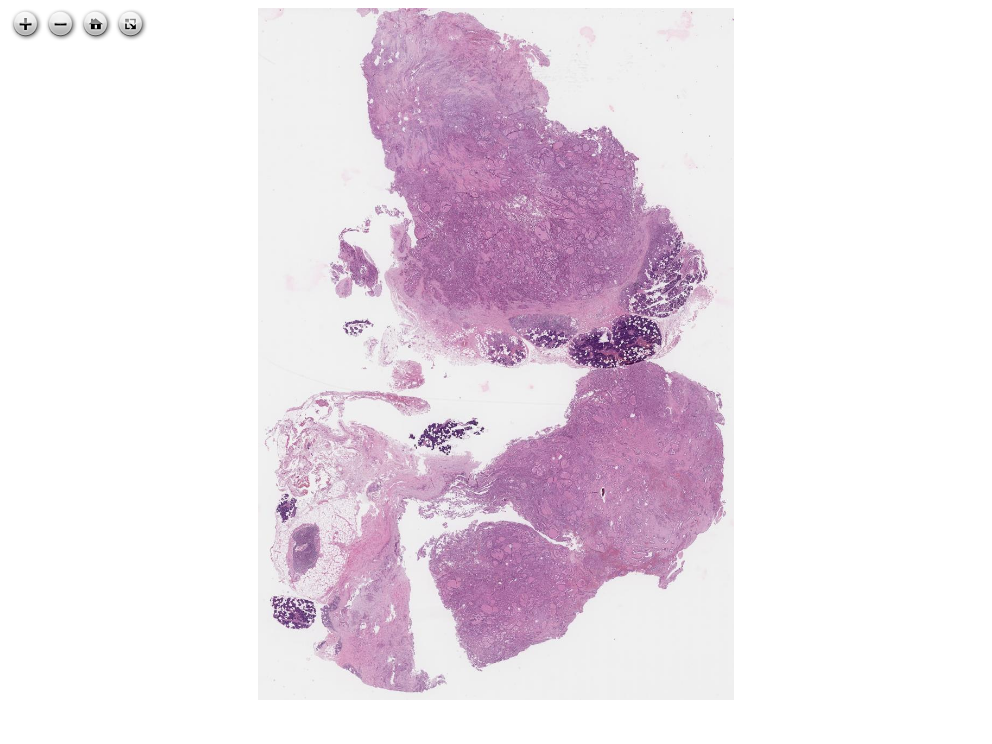

54.1 Mammary analogue secretory carcinoma of salivary gland

** mammary analogue secretory carcinoma of salivary gland**